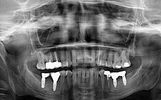

نقص الأسنان

التهاب الأنسجة حول الزرعة